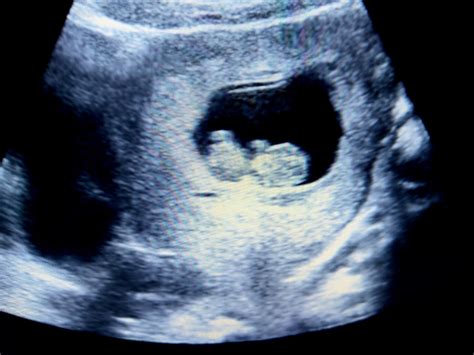

L'Aspetto del Feto alla Decima Settimana: Visto dall'Ecografia

L'ecografia della decima settimana di gravidanza offre una visione chiara della forma generale del feto. È possibile osservare distintamente la testa, il corpo e gli arti. I movimenti del feto, sebbene ancora non percepibili dalla madre, possono essere chiaramente visualizzati durante l'esame. La testa appare ancora sproporzionatamente grande rispetto al corpo, una caratteristica tipica delle prime fasi dello sviluppo, poiché il cervello è in rapida crescita.

Durante l'ecografia, si possono notare i polsi alle estremità delle braccia e lo sviluppo di dita e articolazioni. Entro la fine di questa settimana, la membrana che separa le dita delle mani e dei piedi scompare, permettendo alle dita di separarsi completamente. Questo passaggio è fondamentale, poiché il piccolo inizia ad allenare il riflesso di suzione, essenziale per l'allattamento al seno. Si può anche rilevare il battito cardiaco fetale, che a questa età gestazionale è sorprendentemente rapido, circa 180 battiti al minuto, quasi il doppio rispetto a quello di un adulto. La formazione del padiglione auricolare, la struttura esterna dell'orecchio, è un altro dettaglio visibile. Il feto può sollevare la testa, mostrando movimenti ancora privi di coordinazione.